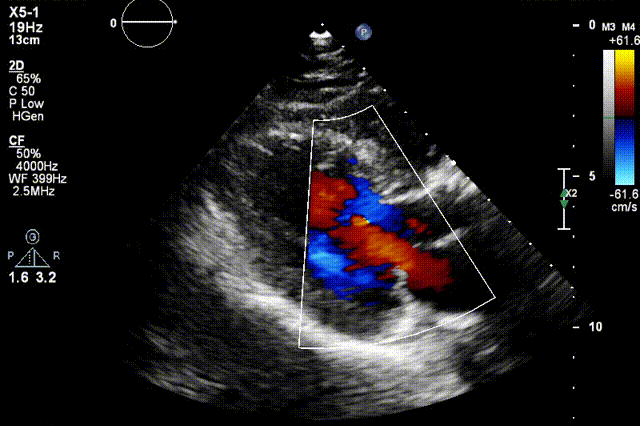

术后24h心超

● EF 68% 。

● 主动脉瓣未见明显反流。经主动脉瓣口收缩期最大流速约1.9m/s,最大压差约15mmHg,心率约95bpm。

● 二尖瓣轻度反流 。

● 三尖瓣轻度反流,最大反流速度约2.9m/s,估测肺动脉收缩压约44mmHg。

● 经左室流出道收缩期最大流速约1.9 m/s。